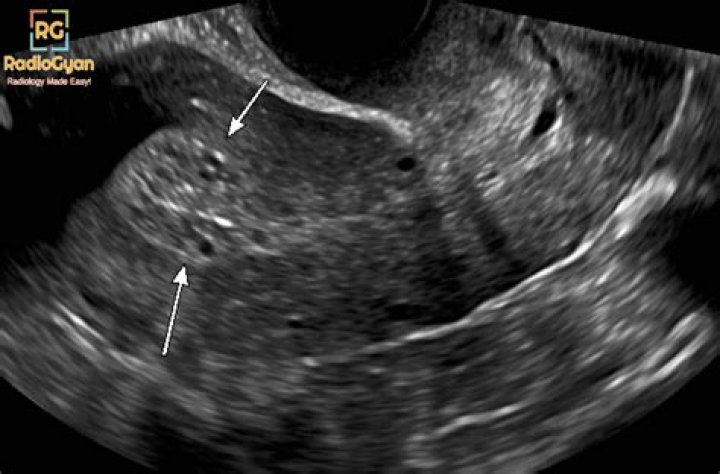

Why would my endometrium be thick?

Endometrial hyperplasia is a condition of the female reproductive system. The lining of the uterus (endometrium) becomes unusually thick because of having too many cells (hyperplasia). It's not cancer, but in certain women, it raises the risk of developing endometrial cancer, a type of uterine cancer.

Among postmenopausal women with vaginal bleeding, an endometrial thickness ≤ 5 mm is generally considered normal, while thicknesses > 5 mm are considered abnormal4, 5.

What is the normal size of endometrial thickness?

suggested upper limit of normal is <5 mm. the risk of carcinoma is ~7% if the endometrium is >5 mm and 0.07% if the endometrium is <5 mm. on hormonal replacement therapy: upper limit is 5 mm.